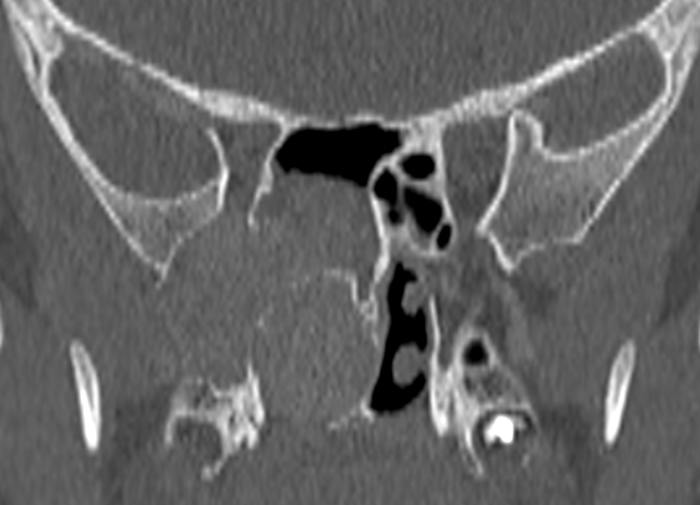

Preoperative sinonasal CT imaging is essential to FESS surgery. Ideally the CT data should be provided in thin-slices (less than 1mm thick) including the full volume of the paranasal sinuses. The images should be available during surgery in a 3 axis viewer, preferably one with the facility for multiplanar reconstruction (MPR).

Before the case, it is helpful to perform an MPR to align the axial slices with the palate and skull-base, while correcting any angulation of the coronal images to obtain symmetric views. Window-levels are optimised for bone definition, rotation corrected for each view, and the views maximised by zoom. We then study the scans from three different perspectives as follows.

Operative CT - the disease

Most FESS is performed for chronic rhinosinusitis. The scan should have been studied well before surgery, but immediate preoperative review is a final opportunity to recognise a sinonasal mass and avoid the unexpected complications of operating on a vascular tumour or meningo / encephalocoele. Findings of an antrochoanal or frontochoanal polyp must be recognised; dictating a surgical approach to allow complete clearance. Bony changes in a unilateral polyp may indicate an inverted papilloma or neoplasia, necessitating histopathologic analysis.

Lamina Papyracea Defects.